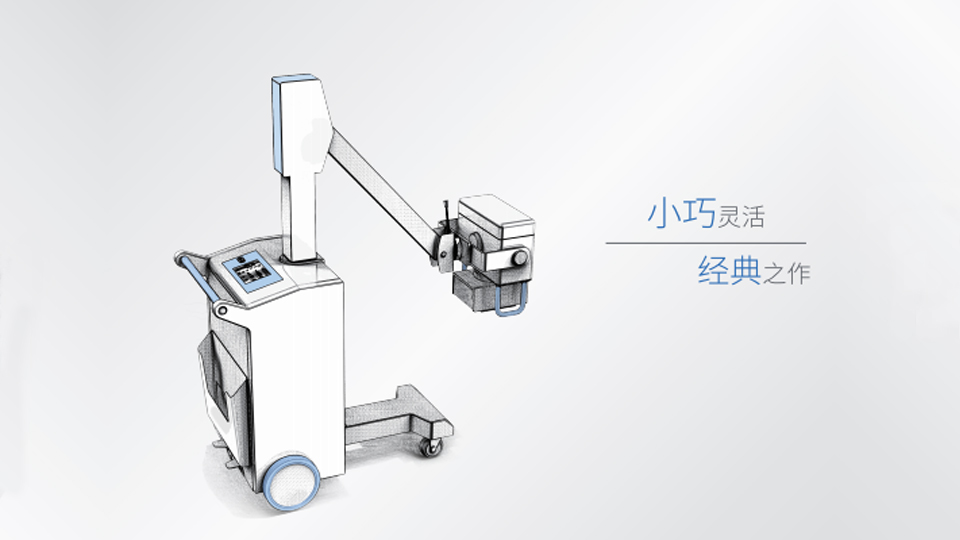

PLX101系列

高頻移動式X射線攝影機

操作簡便 輕巧靈活 PLX101

操作簡便 輕巧靈活 PLX101

● 整機小巧移動輕便靈活;錯位剎車系統,制動可靠